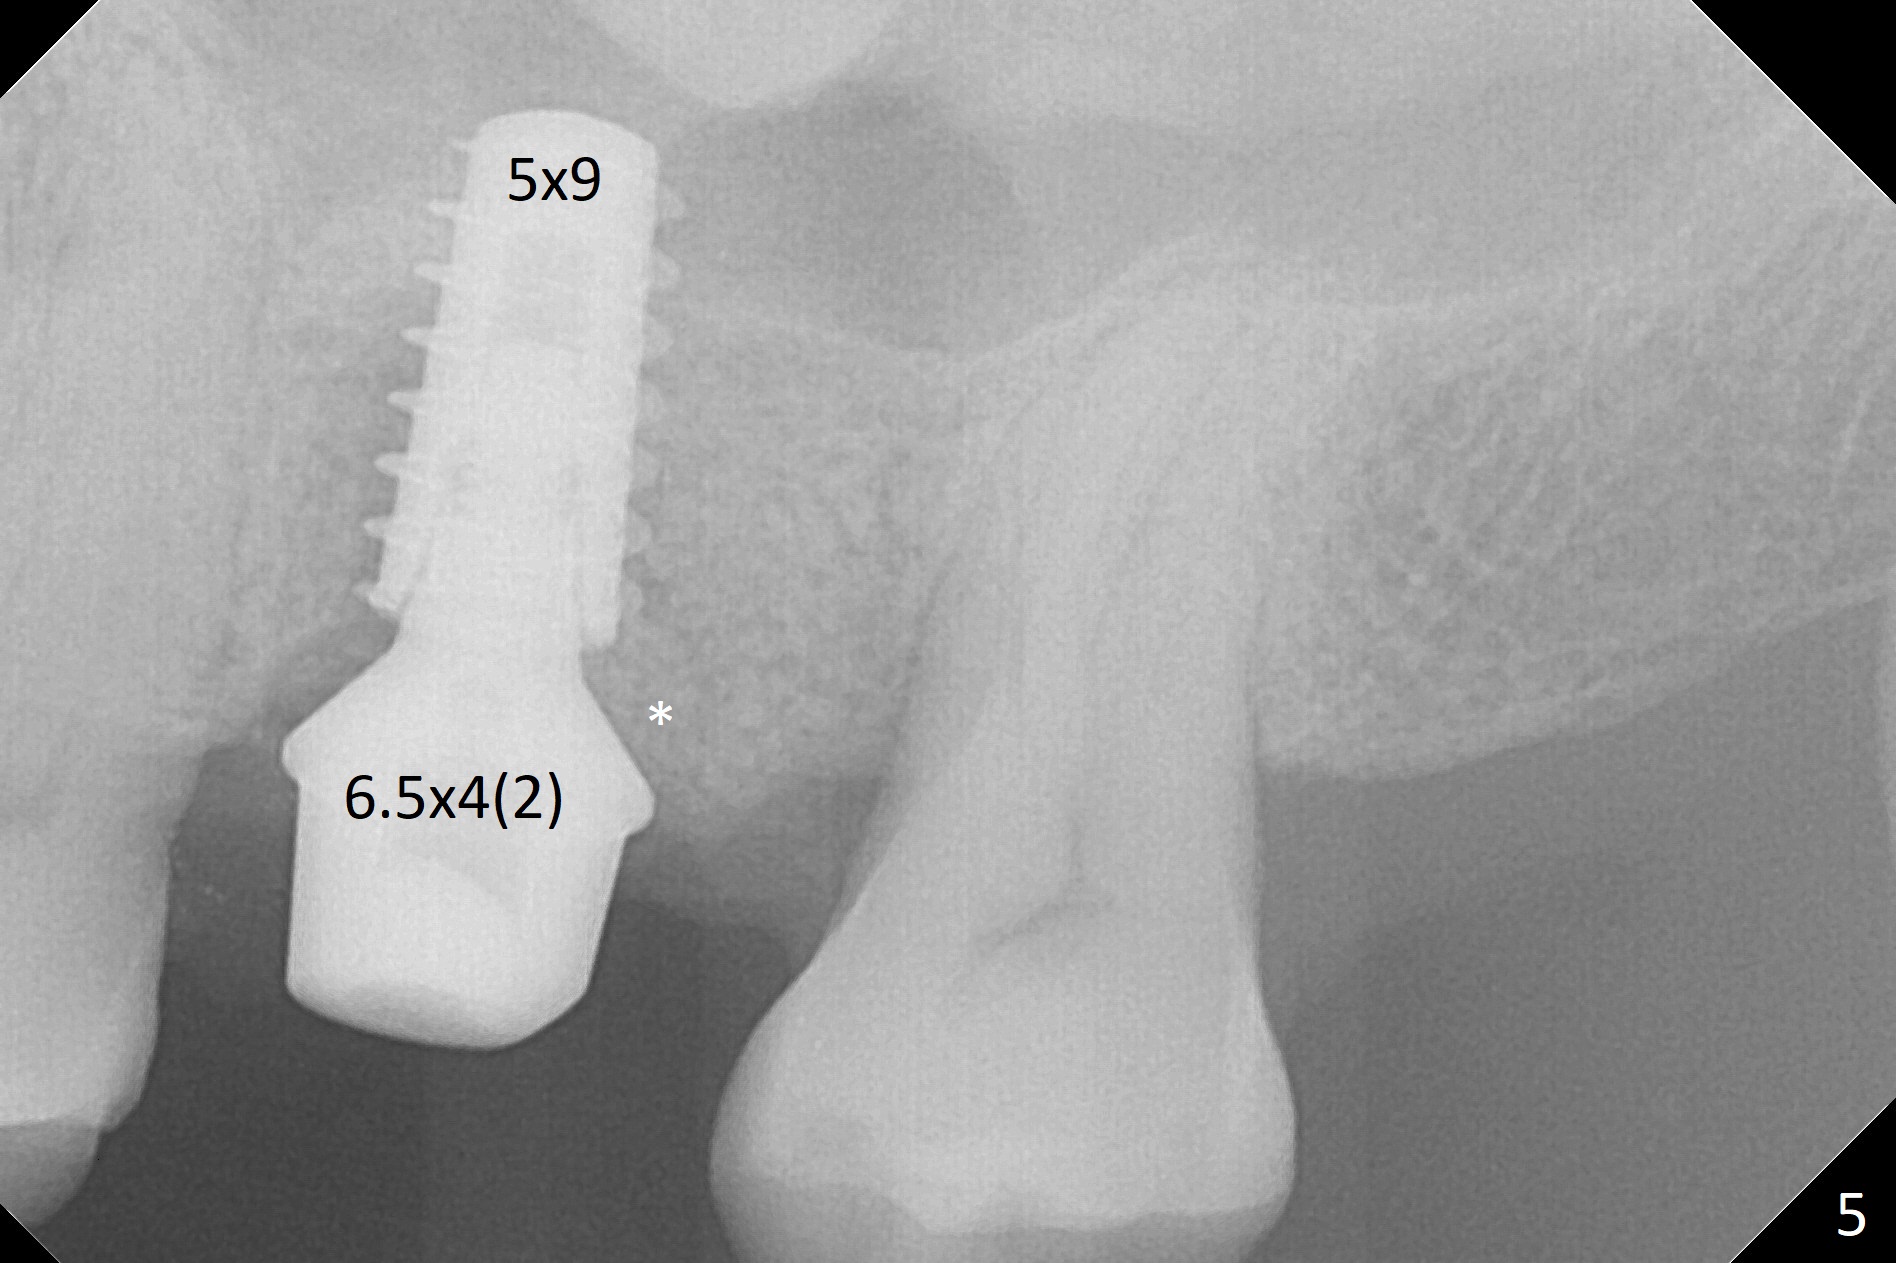

After extraction of the tooth #14 with palatal root fracture (Fig.1 <), sinus membrane perforation is found in the buccal wall of the palatal socket (Fig.2 ^). Osteotomy is initiated in the buccal strut of the septum (Fig.3 *). As the osteotomy increases in diameter, it slides into the mesiobuccal socket (Fig.4). A 5x9 mm implant is placed slightly mesial; after placement of a 6.5x4(2) mm abutment and insertion of collagen plug in the palatal socket, Vera graft is placed in the remaining socket space (Fig.5 *). Nasal hemorrhage persists 1.5 months postop (Fig.6). The distal gingiva is slightly tender and erythematous; a 6x4 mm healing abutment is placed 2.5 months postop (Fig.7,8). Impression is taken after laser gingivectomy 3.5 months postop. The patient feels discomfort at the site 7 days post impression, although the gingiva heals after laser treatment. Two weeks after cementation, the mesial gingiva is mildly tender and the abutment screw is loose. A 6x3 mm healing abutment is placed. The abutment/crown is reseated 10 months postop (Fig.9).